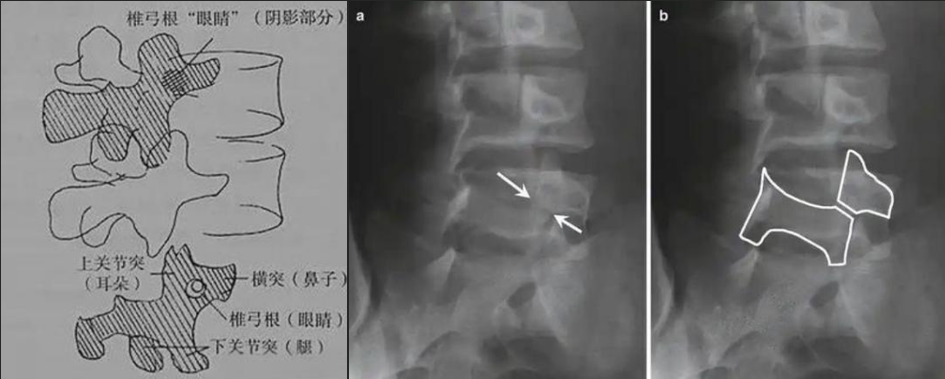

圖a和圖b 腰椎斜位:狗脖“戴項圈征”,診斷椎體椎弓峽部裂

椎弓根峽部是椎體后部椎弓上最狹窄、最薄弱、但應(yīng)力最集中的部位,在常規(guī)腰椎X線正側(cè)位上,因腰椎其他結(jié)構(gòu)的重疊顯示不清,但是在腰椎斜位上,能夠清楚完美地展現(xiàn)出來,若其在斜位片上表現(xiàn)為不連續(xù),則可診斷為椎弓根峽部裂,即腰椎的關(guān)鍵承重部分的骨質(zhì)斷裂,這是導(dǎo)致青少年和運動員腰痛的主要原因。

在腰椎斜位片上,腰椎的附件結(jié)構(gòu)形成了一個經(jīng)典的“斯科蒂狗”圖案,其中“狗脖子”處即代表椎弓根峽部,若“狗脖子”上出現(xiàn)了一條透亮清晰的線,就像給狗戴了一條“項鏈”,即“戴項圈征”,這是診斷椎弓峽部裂的直接證據(jù)。